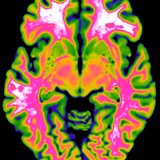

Biological Psychology & Imaging

Claus Lamm, University of Vienna, Faculty of Psychology, together with Rupert Lanzenberger, Medical University of Vienna, Department of Psychiatry and Psychotherapy: Multimodal Neuroimaging in Clinical Neurosciences: Assessment of neurobiological markers for psychiatric disorders.

Roland Beisteiner, MedUni Vienna, Department of Neurology and Tecumseh Fitch, University of Vienna, Department of Cognitive Biology

Roland Beisteiner, Medical University of Vienna, Department of Neurology, in collaboration with Tecumseh Fitch, University of Vienna, Faculty of Life Sciences: Shared Neural Resources for Music and Language: Verification and Clinical Exploitation.